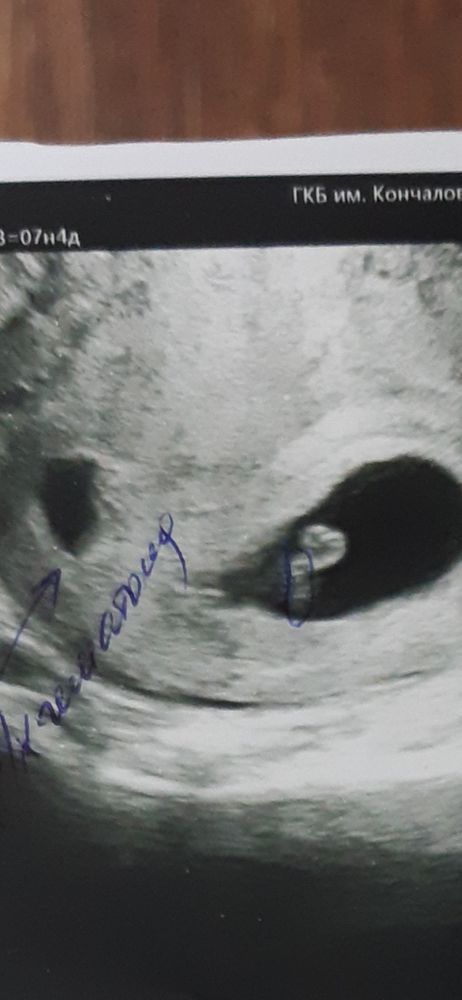

Ретрохорионическая жидкость

Всё о нашей беременностиИменно так. Не гематома. Врач УЗИ сказал, что на гематому не похоже, и на деформированное ПЯ тоже. Говорит, через пару недель рассосётся.

Сравнила размеры с прошлым УЗИ (правда, на прошлом УЗИ это назвали таки гематомой) - было 21*12, щас 23*24. То есть растет.

Виолетта, о! Спасибо за фото. А то везде гематома выглядит не такой черной.